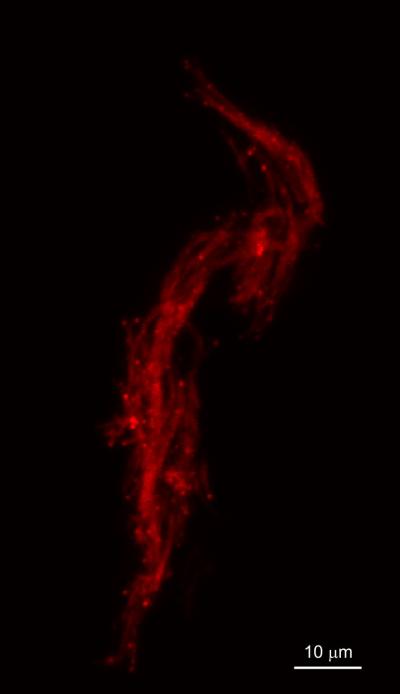

These studies are conducted in zebrafish, an animal model for tuberculosis. The fish's embryos and small fry are transparent. Researchers can see through their skin to observe their organs, tissues and cells and the internal appearance of some infections, for example, the bacterial cording of TB.

When the TB bacteria escape the confines of the scavenger cells, "they grow exuberantly in the extracellular environment," Roca and Ramakrishnan said.